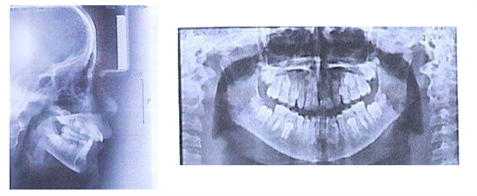

A 13-year-old patient reported to the Department of Dento-Facial Orthopedics of the Dental Consultation and Treatment Center (CCTD) of the Ibn Rochd University Hospital in Casablanca, Morocco, with an aesthetic chief complaint which was projection of the incisors and unpleasant profile. No pathological background information was reported according to her medical history. Clinical examination (Figure 1) showed a convex profile with accentuated labiomental groove. The patient was in the permanent dentition stage. Concerning the inter-arch relationship we recorded a Class II molars and canines on the left side and class I canine and molar on the right side, with a deviation of the inter incisal median on the left side of mandibular origin, with 6 mm of overjet and 4 mm of overbite. She had mild maxillary and mandibular arch crowding. The panoramic radiograph (Figure 2) showed normal bone and tooth forms with developing third molars. Cephalometric analysis (Table 1) revealed a Class II skeletal base (ANB = 10˚) with normotrusive maxilla, retrusive mandible (SNA = 84˚, SNB = 74˚). Moreover, the patient had a skeletally normal face (GoGn/SN = 33˚, FMA = 22˚). In addition, the upper incisor was normoclined (I/NA = 22˚/4mm), and lower incisors were proclined (I/NB = 37˚/7mm).

Figure 2. Pre-treatment lateral cephalogram and panoramic radiograph treatment plan and progress.